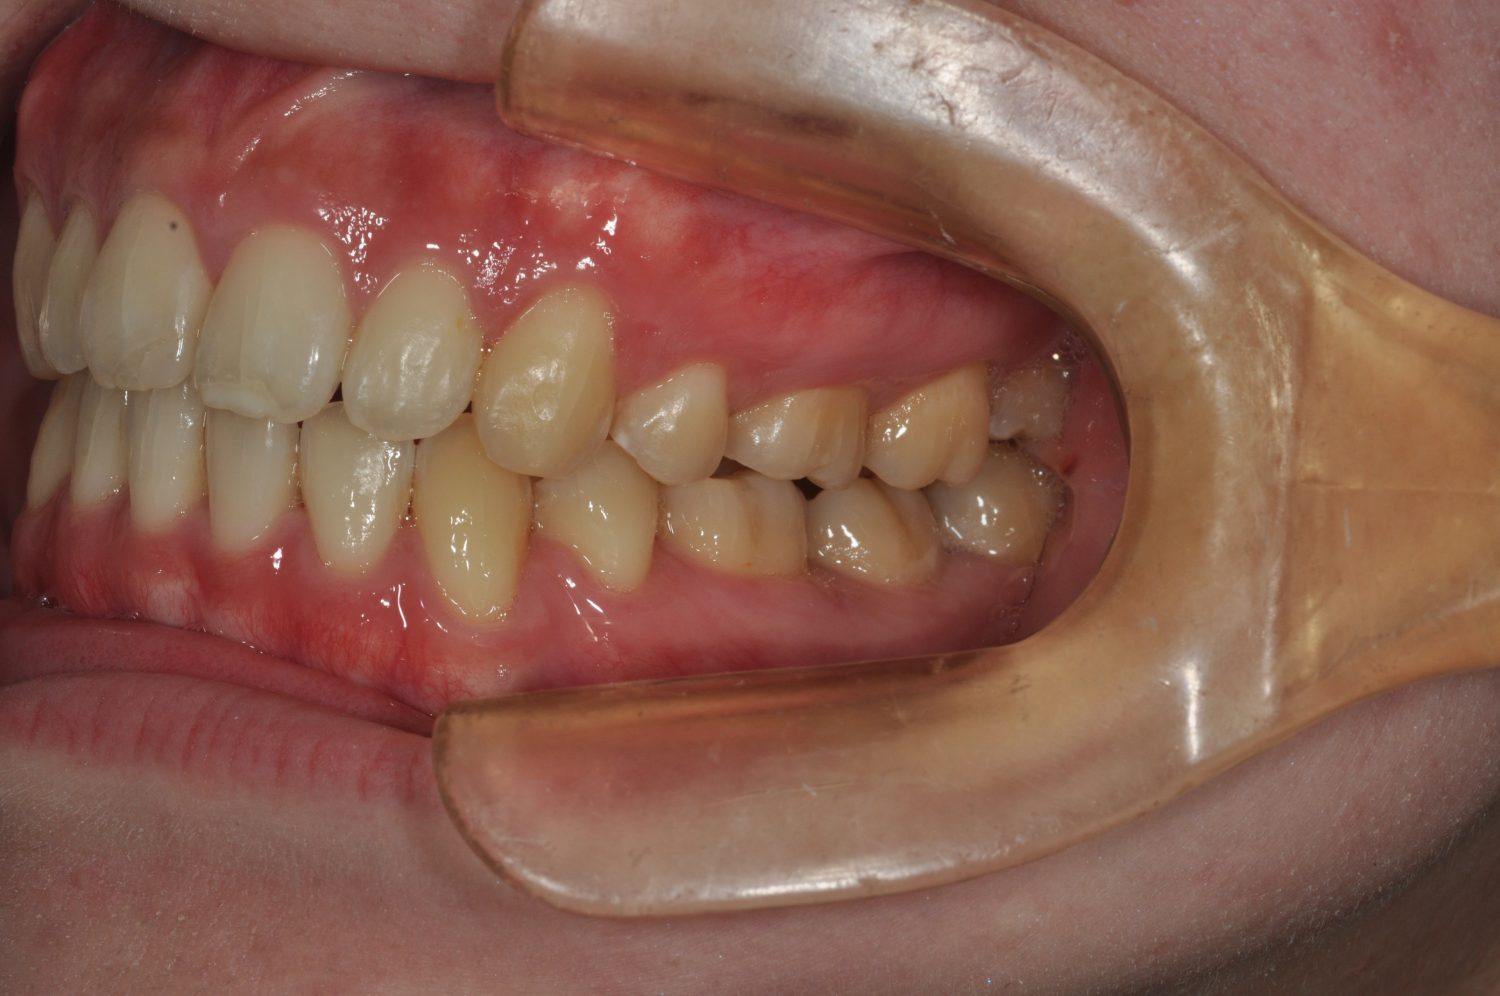

| 主訴 | 口唇の突出感 |

| 治療内容 | 小臼歯抜歯によるマルチブラケット治療 |

| 治療期間 | 1年7ヶ月 |

| 治療回数 | 21回 |

| 想定されたリスク | 矯正後、後戻りする可能性がありました。また、歯根吸収や歯肉退縮のリスクがありました。 |